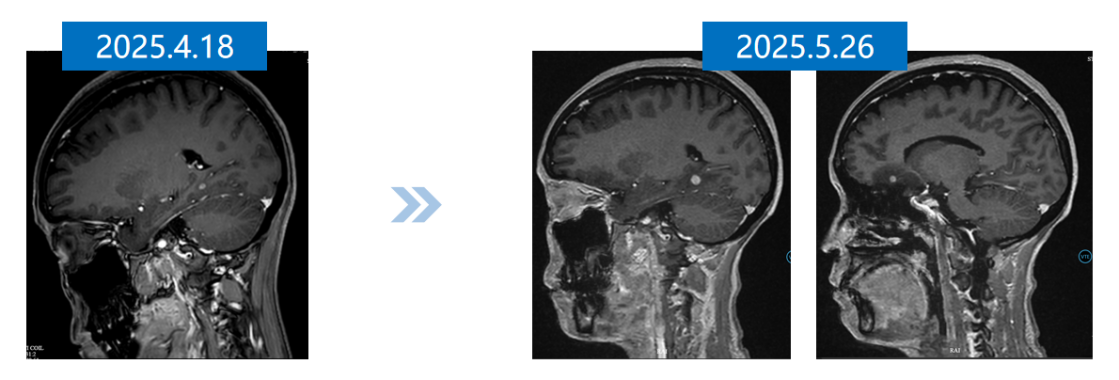

• 颅脑增强MRI(2025-4-18): 右侧颞枕部单发转移瘤,长径约3mm。

12.png

全身骨显像及颅脑增强MRI

2025年5月26日,颅内MRI示颅内病灶进展。

图片111.png

一线治疗前后颅内MRI